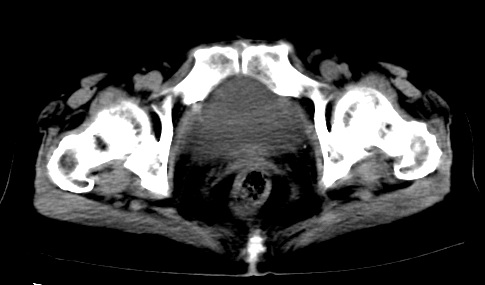

标题: CT23975:女61岁,腹部不适,明显消瘦 [打印本页]

标题: CT23975:女61岁,腹部不适,明显消瘦

既往5年前卵巢癌行子宫及附件切除,右乳癌术后一年,考虑腹膜转移?

大量腹水,考虑腹膜转移。肝脏低密度灶。1囊肿,2转移。

1)结合病史,考虑腹膜及网膜转移瘤。2)肝脏多发性低密度灶,不排除转移瘤。3)大量腹水。

考虑卵巢癌行子宫术后复发,并肝、腹腔 、大网膜转移可能性大。

大量腹水。